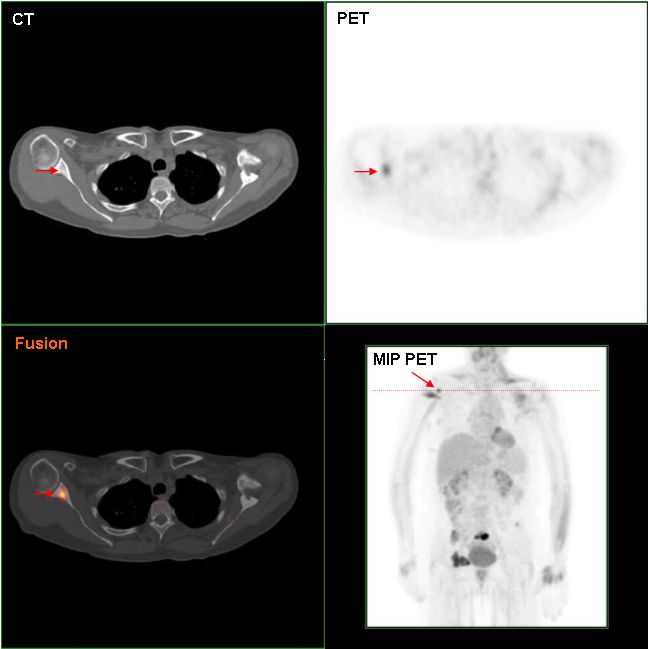

The TNM staging system, which stands for tumor (T), nodes (N), and metastases (M), determines the prognosis for breast cancer.

Although metastasis is the most crucial element, most patients show up before metastasis happens.

Given that metastasis is uncommon at presentation, spread to axillary lymph nodes is the most helpful prognostic marker.

With sentinel lymph node biopsy, axillary lymph nodes can be assessed for malignant cells.